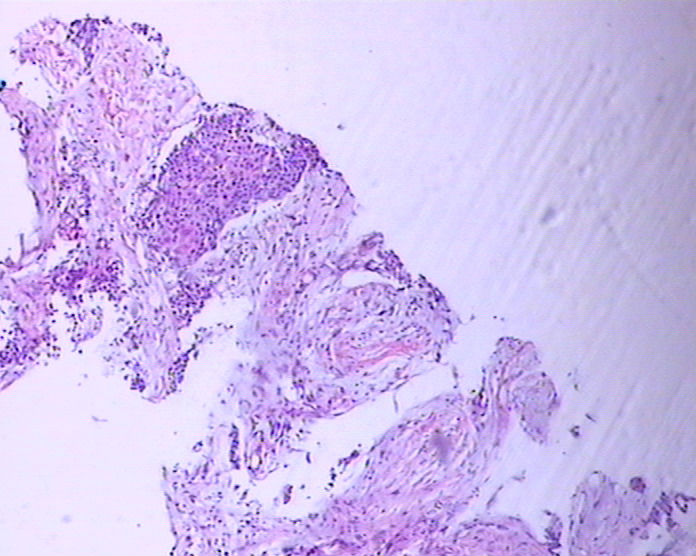

患者男性,51岁,发现右纵膈肿物,行穿刺活检。

参考诊断

鳞癌?

1。胸腺癌?

2.低分化鳞癌?

胸腺癌?